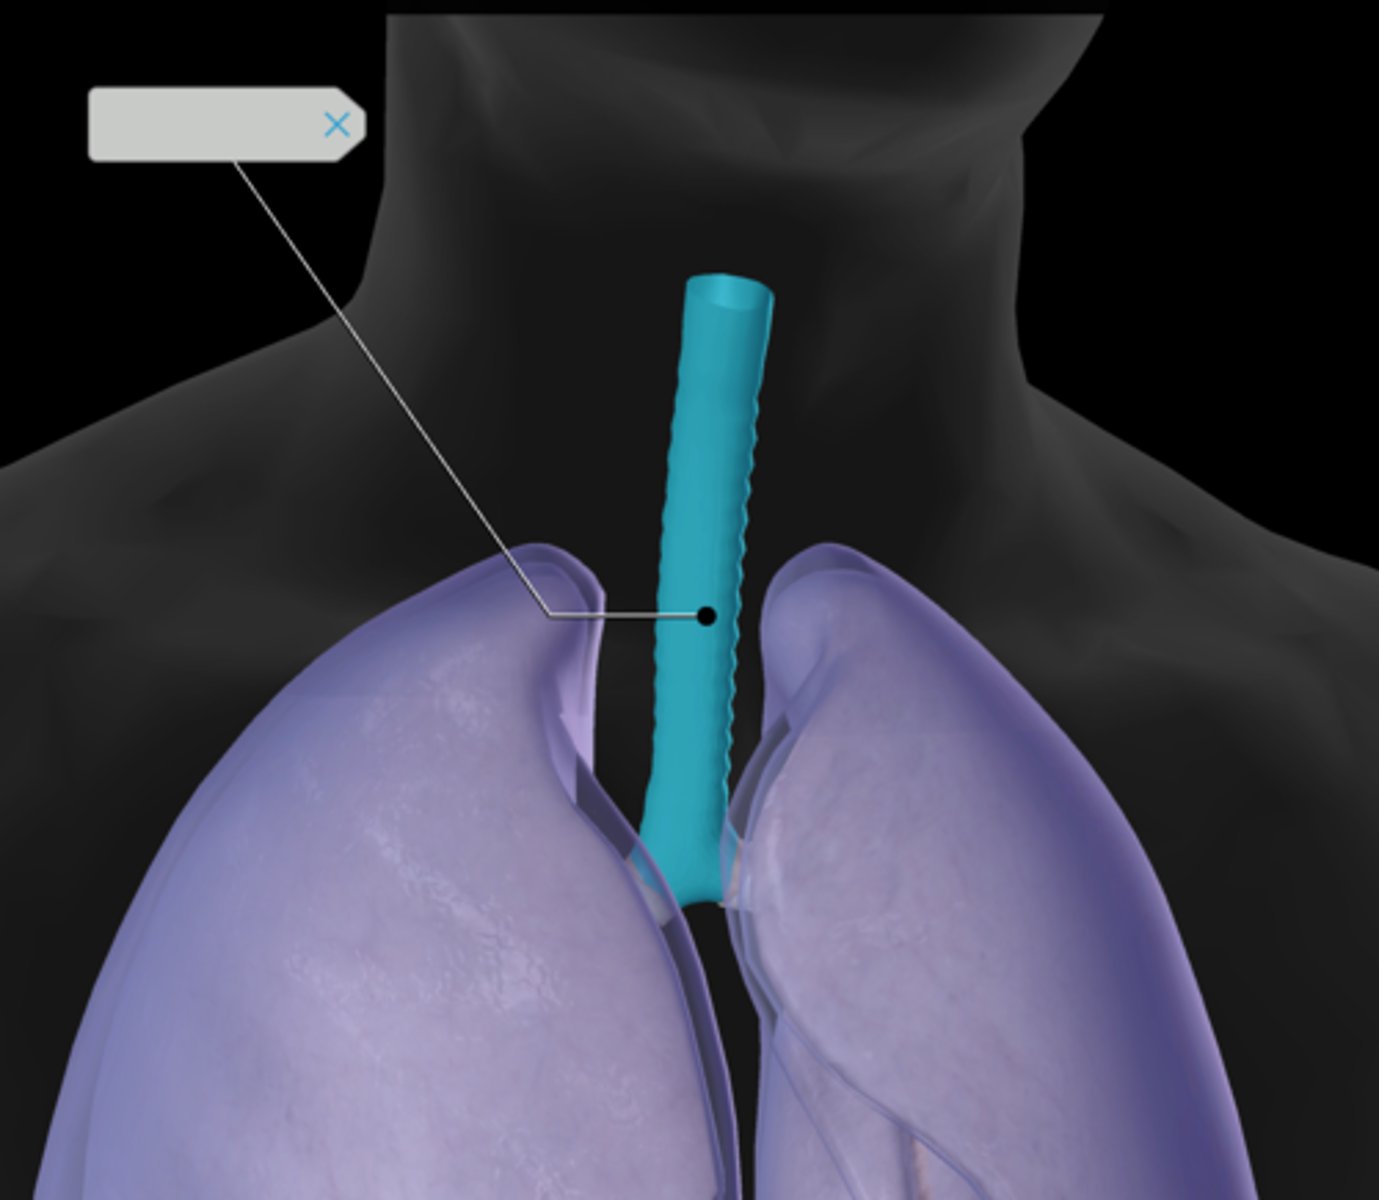

Trachea